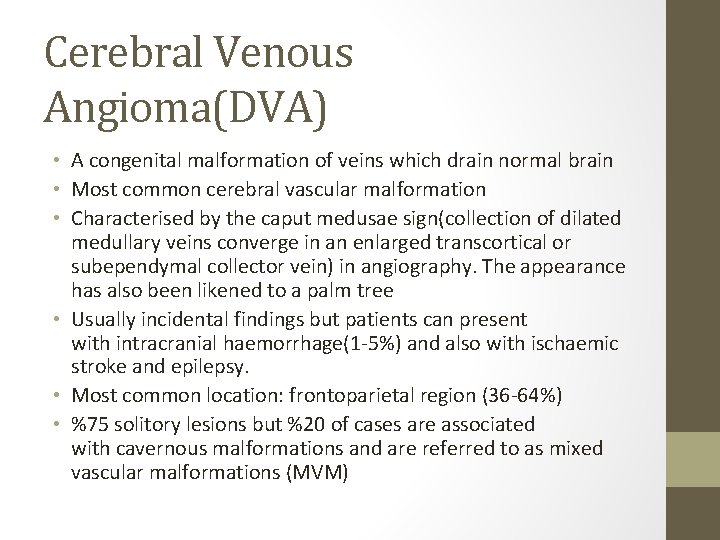

Cerebral Venous Angioma(DVA) • A congenital malformation of veins which drain normal brain • Most common cerebral vascular malformation • Characterised by the caput medusae sign(collection of dilated medullary veins converge in an enlarged transcortical or subependymal collector vein) in angiography. The appearance has also been likened to a palm tree • Usually incidental findings but patients can present with intracranial haemorrhage(1 -5%) and also with ischaemic stroke and epilepsy. • Most common location: frontoparietal region (36 -64%) • %75 solitory lesions but %20 of cases are associated with cavernous malformations and are referred to as mixed vascular malformations (MVM)